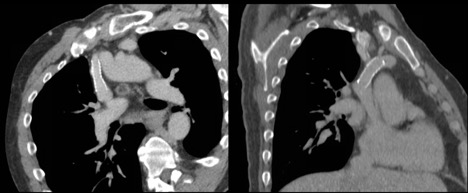

Subsequently, the decision was made to proceed with a venogram and possible SVC stent placement. If this were unsuccessful, he would undergo thoracoscopic thoracic duct ligation. He was found to have hemodynamically significant stenosis of the superior SVC resulting in a 21 mm Hg pressure gradient between the left innominate vein and central SVC. He underwent successful stent placement with decompression of previously visualized left thoracic venous collaterals (Figure 3). After stent placement the pressure gradient was reduced to 1 mm Hg. The patient subsequently has remained stable, with resolution of his chylothorax without the need for further interventions.